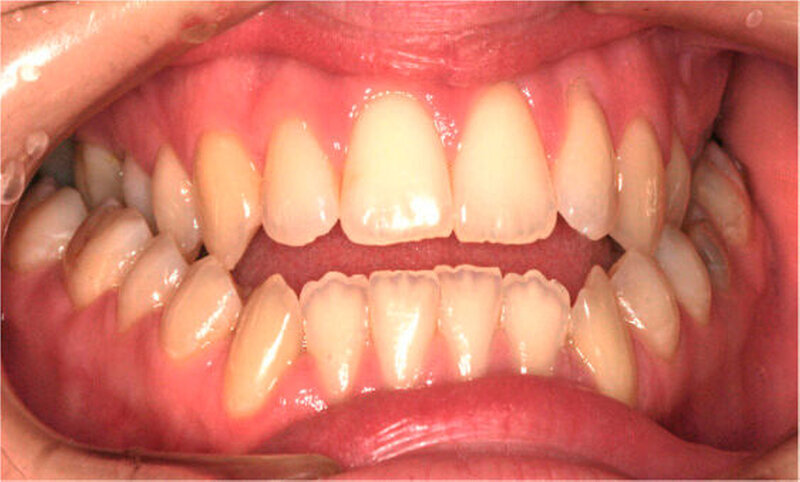

Die Patientin war zu Behandlungsbeginn 26 Jahre alt. Sie wies eine ausgeprägte skelettale Mesialbisslage (Wits: – 15,6 mm) mit retrognather Maxilla (SNA: 76°) und prognather Mandibula (SNB 87°) bei zusätzlicher Mittelgesichtshypoplasie auf (Abbildung 1a). Intraoral bestanden ein frontal offener Biss und eine transversale Enge im Oberkiefer mit zirkulärem Kreuzbiss (Abbildung 1b).